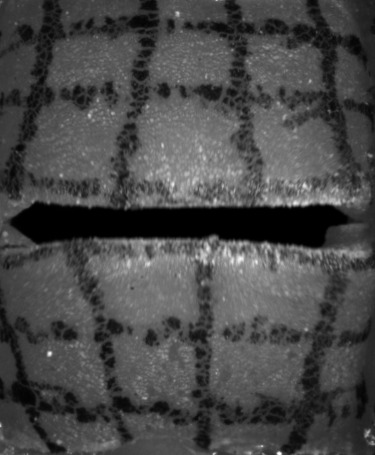

High-speed Camera

The high-speed camera provides a sequence of mono-chromatic images, as shown in Fig. 3. These images can be described as a function of intensities with an image resolution , the screen-space coordinates and with being the currently sampled frame of the video with many frames in total. Then, and denote the estimated motion of the screen-space coordinate at time along the longitudinal and lateral axis, respectively, resulting in the motion vector field:

We applied the sparse to dense optical flow algorithm based on the Lucas-Kanade feature tracker with pyramids by [25], which is available in OpenCV [26]. Such dense optical flow algorithm estimates a motion for every pixel of the input image, but tends to oversmooth flows (see Fig. 4(a)), which produces artifacts at edges. To mitigate this problem, we apply a mask (see Fig. 4(b)), which helps to distinguish the vocal folds from the gap between them. We use the intensity values for the mask segmentation with a subsequent median filter for more robustness to noise. Using the mask (see Fig. 4(c)), we set the motion vectors inside the gap explicitly to zero vectors, since there is no vocal fold movement. For consistency with the remaining data, the motion in the image plane is converted to physical domain units. The high-speed images and the resulting optical flows are discrete in space (individual pixels) and in time (individual frames). We interpolate the resulting discrete vector piecewise bilinearly in space with continuity and we interpolate quadratically with continuity in time to extract a continuous time-dependent two-dimensional vector field.